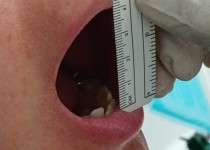

만 52세 전악 상악, 하악 전체 임플란트…

만 56세 상 하악 임플란트 증례